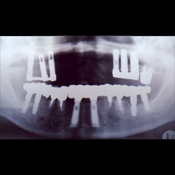

症例 13)

60代 女性 上顎は左右に6本のインプラントを埋入し、着脱式のメタルファーム義歯を作製。下顎は左右の奥歯に2本づつ計4本と、前歯部に2本の合計6本のインプラントを埋入し、それぞれPGAクラウンとメタルボンドセラミッククラウン(白い歯)にて修復を実施。

上顎前歯部の歯槽骨(歯、インプラントを支える骨)が吸収されており少ないです。

上顎の小臼歯は歯周病の進行が強く、抜歯することとしました。

まず、下顎に計6本のインプラント埋入と、前歯部にメタルボンドセラミッククラウン(白い歯)と臼歯部にゴールドクラウンを装着し、上顎右側の奥歯に3本のインプラントを埋入、バーアタッチメントを用いて取り外しの義歯を固定します。

さらに左奥歯に3本のインプラントを埋入し、コーヌスアタッチメントとし、上顎に装着している義歯を小さくし、口腔内での装着感を増すことにしました。